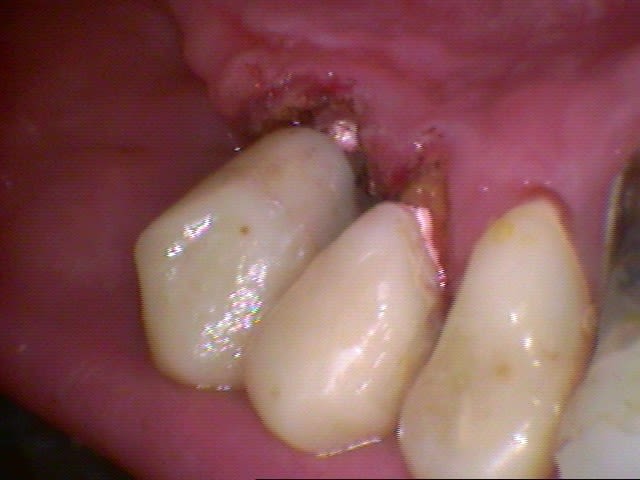

Tu as raison voila un patient que j'avais massacré au cerec voici 9 ans, il est revenu dans sa belle province la semaine dernière et me demande ce que je pense du boulot qu'il s'est fait faire en région parisienne il y a 4 ans.

Alors le cerec, c'est ce qui est transparent, avec deux implants de chez nobel , la céramique c'est de la vitamarkII et le super boulot à l'ancienne de Paris c'est le secteur 2, celui qu'on voit bien à la radio d'aujourd'hui.

Dommage que je n'ai pas le cliché pano de l'époque, il ya 9 ans, mais c'était clean en ce temps là.

Je trouve qu'il s'est vite dégradé le pauvre gars.